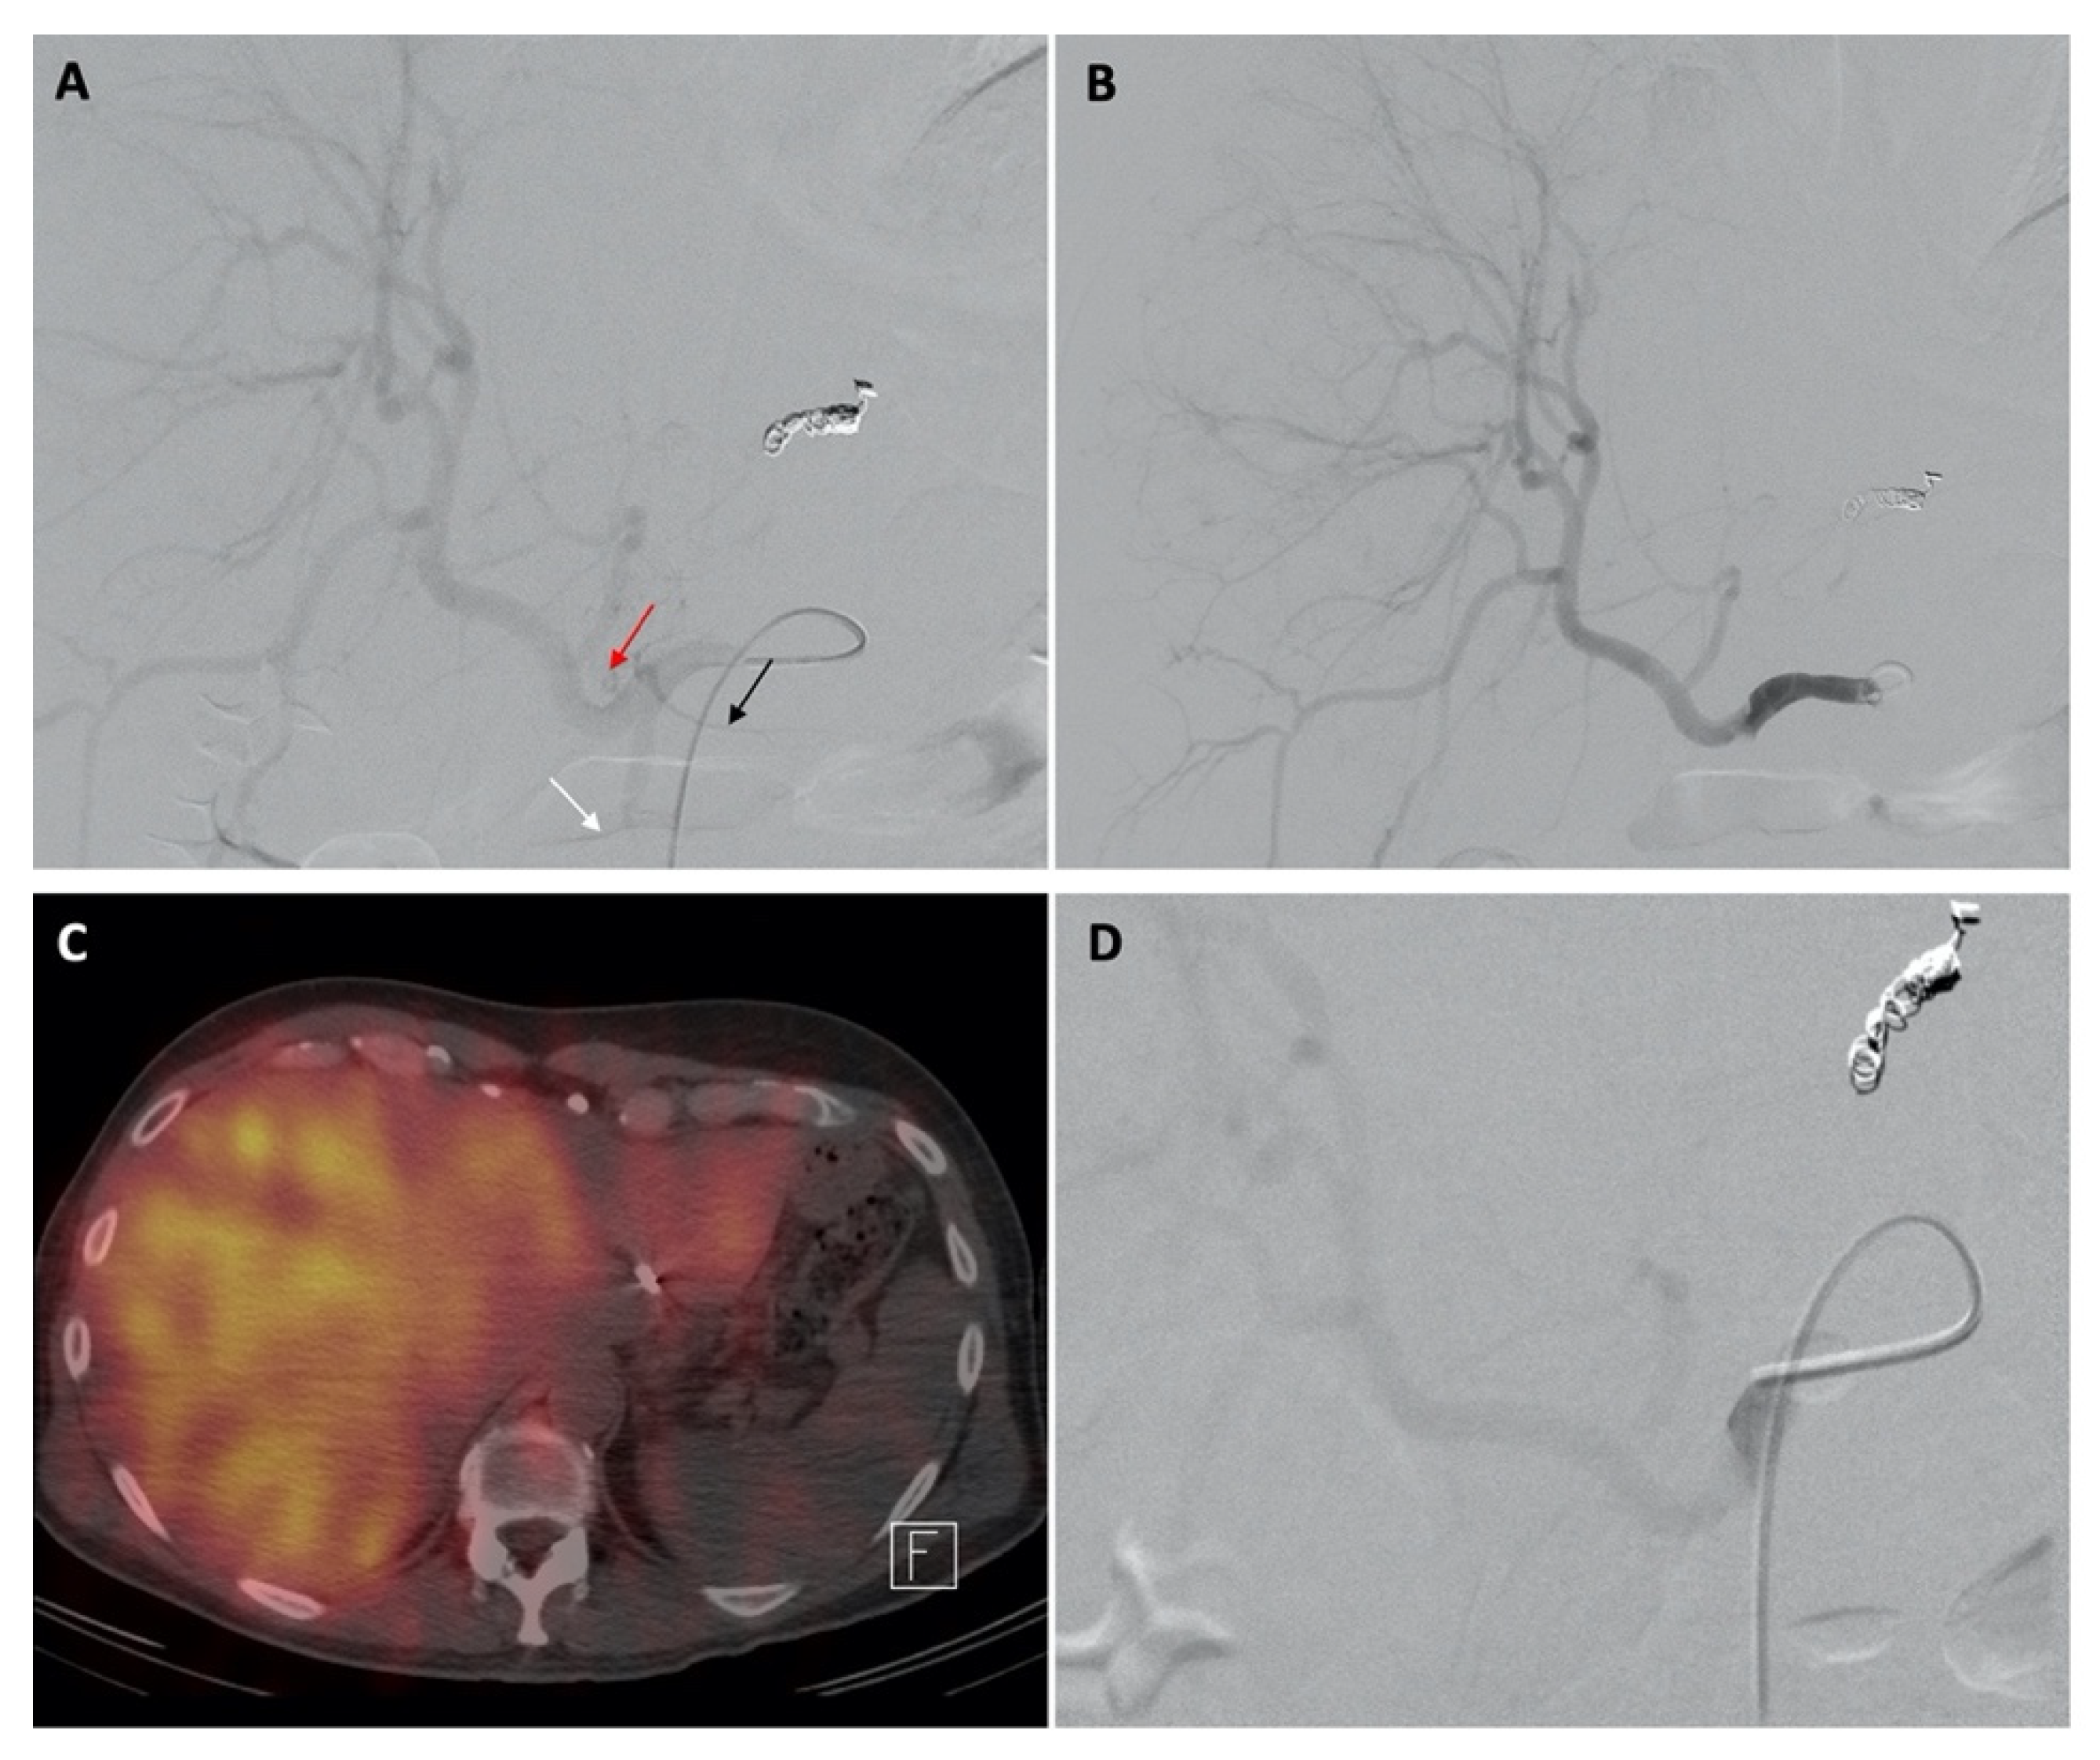

Temporary Reversal of Hepatoenteric Collaterals during 90Y Radioembolization Planning and Administration

Habibollahi, P.; Odisio, B.C.; Gurusamy, V.; Kuban, J.D.; Avritscher, R.; Abdelsalam, M.E.; Chasen, B.A.; Murthy, R.; Mahvash, A. Temporary Reversal of Hepatoenteric Collaterals during 90Y Radioembolization Planning and Administration. Curr. Oncol. 2022, 29, 9582-9592. https://doi.org/10.3390/curroncol29120753